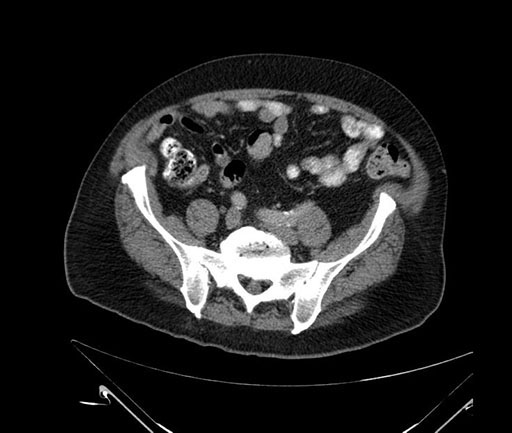

Whipple (pancreaticoduodenectomy) [case 7]

Imaging Analysis

Look through the patient's CT scan to identify any areas of concern for the necessary procedure.

Based on your CT findings, which issue(s) would give reason for "planned slowing down moment(s)" in this case?

Considering a standard Whipple procedure, what step(s) of the operation would you do differently in this case?